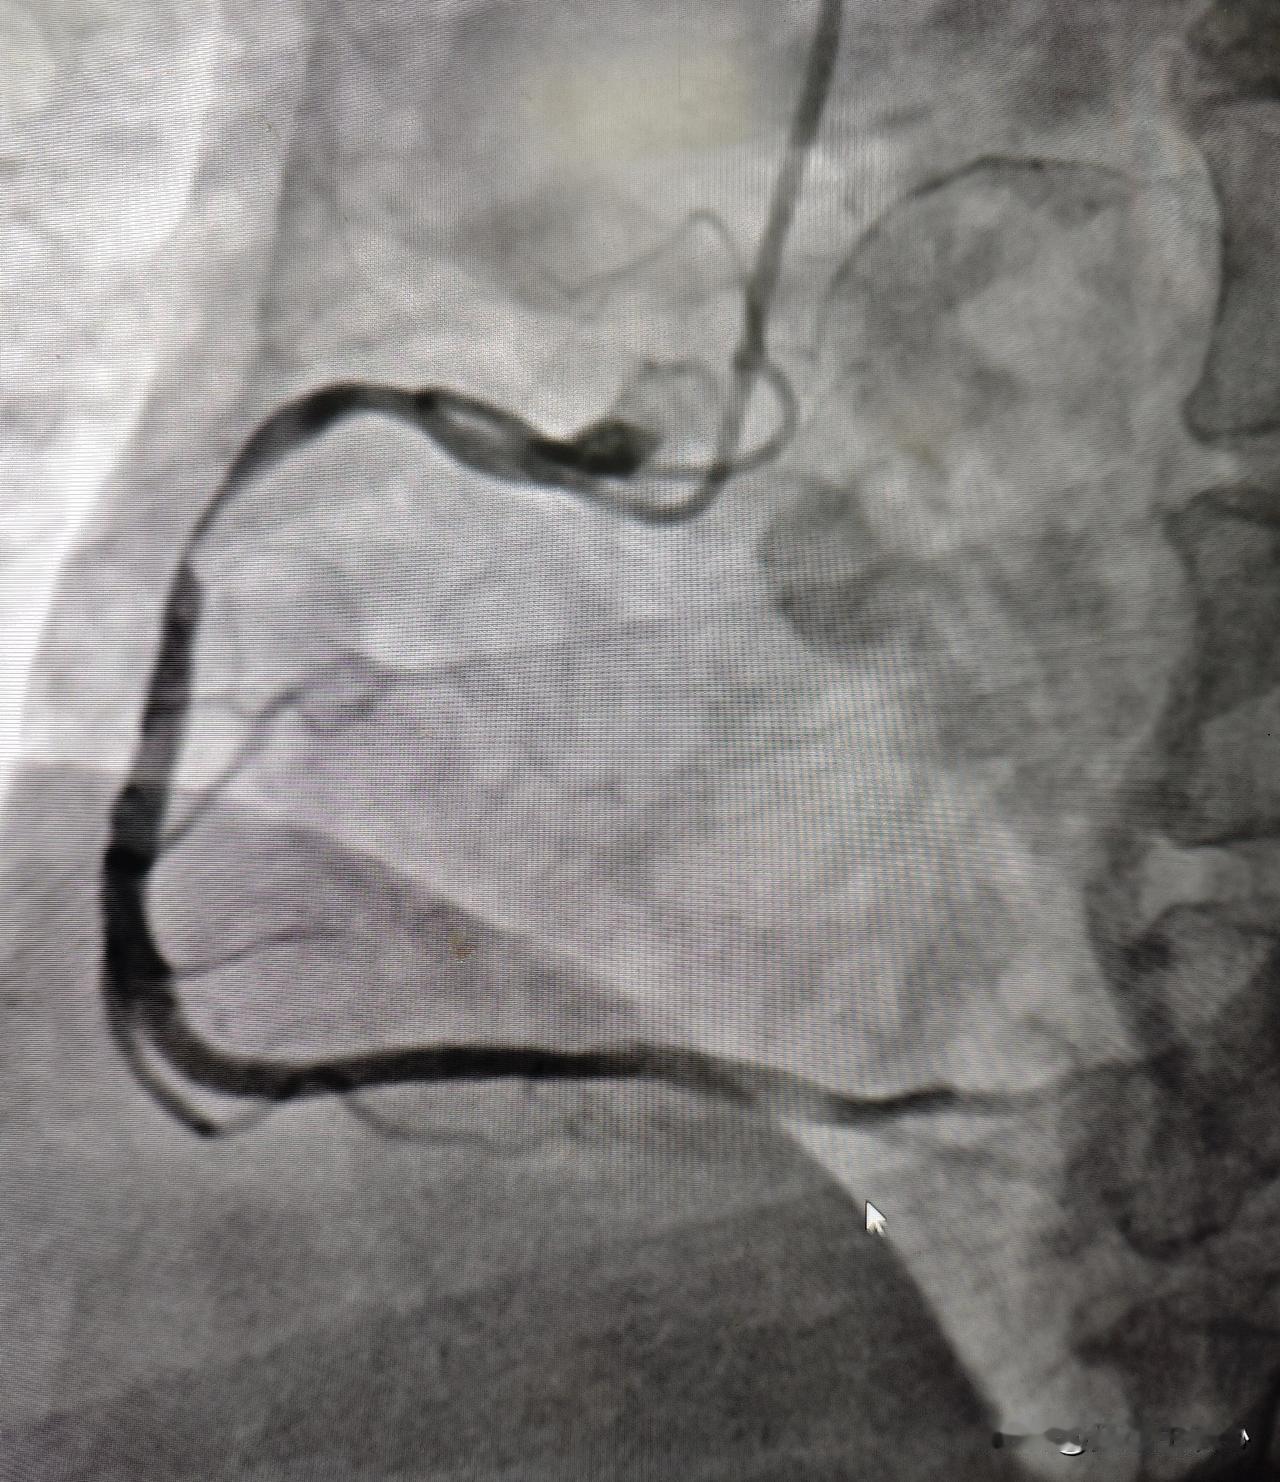

32 岁年轻患者突发心肌梗塞。国庆假期已经接近尾声,刚一接班急诊电话就来了,一个 32 岁男性患者突发胸痛一小时,送到医院做心电图发现下壁导联 ST 段抬高,考虑急性心肌梗塞。赶紧绿色通道直达手术室,一边手术,一边让家属办住院手续,同步进行,争分夺秒,最快速度挽救心肌。 迅速穿刺好桡动脉做冠脉造影检查,发现右冠状动脉重度狭窄,有血栓形成,导丝迅速通过病变部位,用球囊扩张血管,植入支架后血流恢复正常。 这么年轻,血管就一塌糊涂,到处都是动脉硬化斑块,此次急诊手术做了堵塞最严重的地方,还剩做前降支严重堵塞的,等病情稳定以后还需要再做支架手术,听到血管堵塞的位置这么多,这个年轻小伙子一时有点难以接受,又冠心病需要终身吃药,直呼完了完了[流泪] 询问患者有没有什么危险因素,回答说就是抽烟和高血压,其他没了。近几年年轻心梗患者越来越多,跟抽烟、不健康的生活方式关系很大。诸位朋友,不管年龄大不大,健康第一位,保护好自己的心脏。心梗 心梗症状 心梗征兆 心肌梗死